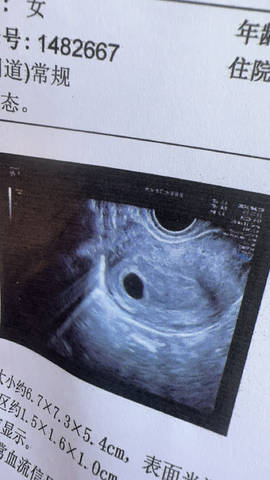

问医生几周她不懂,我月经乱不知道 每周都去复查,一开始说宫外,一下子又说空囊?现在看不到卵黄囊胎心胎芽,焦虑?3.15测了没有,4.3号测出来两条杠

从这样来看的话,应该是怀孕6周的一个样子了呀,你可以后期定期做好复查,到时候看一下情况吧